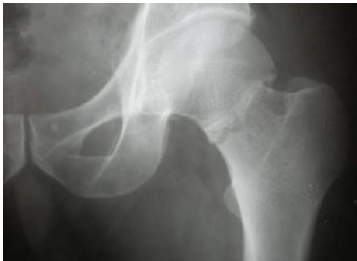

Uma mulher de 70 anos de idade, eutrófica, caiu da própria altura. Após a queda, apresentou intensa dor e foi encaminhada para a emergência, onde foram solicitados raios X de fêmur esquerdo, representados na imagem.

Acerca desse caso clínico, julgue o item a seguir.